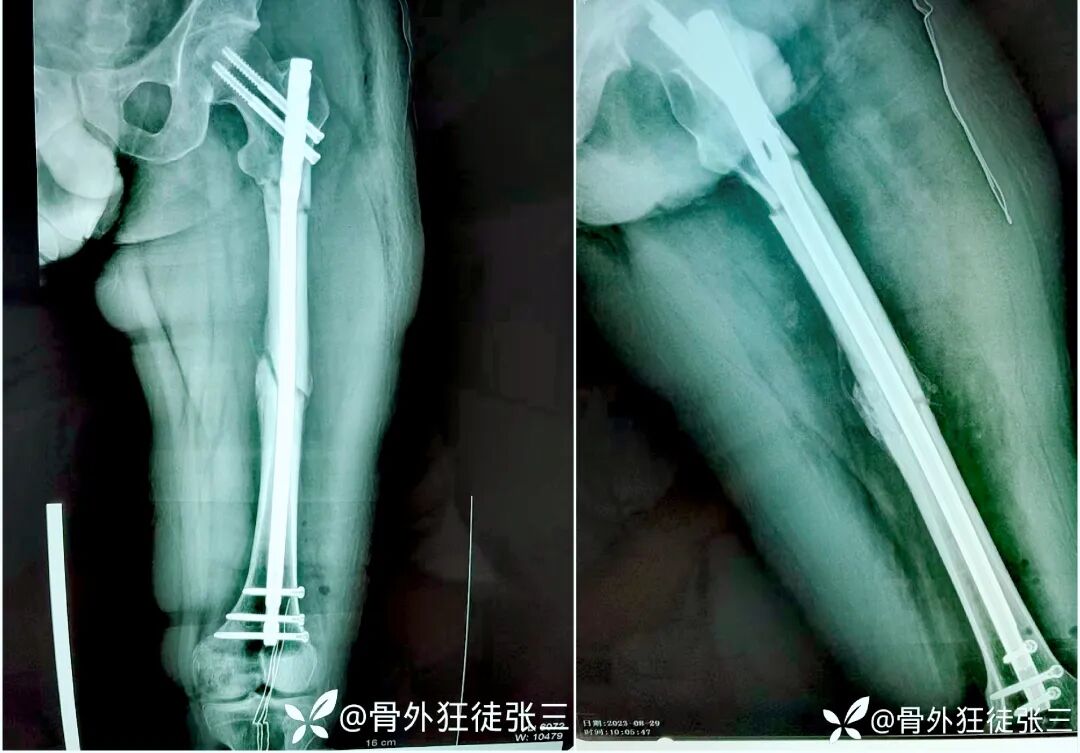

青年男性,股骨干骨折,切开复位,逆行髓内钉

术后3个月,弃拐负重,正常上班

取出内固定,恢复自由身